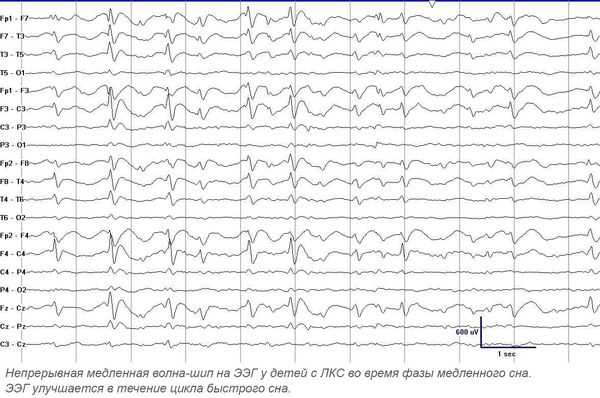

Этиология остается неизвестной. У 12% пациентов в семейном анамнезе выявляются случаи эпилепсии у родственников, однако синдром Ландау-Клеффнера не имеет прослеживаемый наследственный характер. Предполагается, что патология представляет собой дисфункцию речевой зоны коры мозга, обусловленную эпилептогенной активностью. В пользу этой гипотезы свидетельствует необычайная продолжительность эпилептиформной активности, регистрируемой на ЭЭГ, у многих пациентов носящей почти непрерывный характер всю фазу медленного сна. В редких случаях синдром является симптоматическим. В литературе описано его возникновение при астроцитоме головного мозга, локализующейся в височной доле, церебральном цистицеркозе, черепно-мозговой травме.

При проведении ЭЭГ у всех больных выявляют эпилептиформные изменения. Патогномоничны высокие пик-волны, регистрируемые в височных областях и наиболее выраженные в фазу медленного сна. Последнее диктует необходимость проведения ЭЭГ сна, которая зачастую регистрирует электрический эпилептический статус медленного сна — постоянную диффузную эпилептическую активность в период медленноволнового сна. При отсутствии изменении на ЭЭГ сна рекомендуется длительное ЭЭГ-мониторирование.

Утверждённой классификации по данным ЭЭГ нет. Изменения на ЭЭГ при ЛКС имеют чёткую зависимость от возраста: возникают в 3-9 лет и, как правило, постепенно исчезают к 13-15 годам [1] [7] [8] . Продолжительность максимально выраженных диффузных ЭЭГ-аномалий составляет в среднем от 1 до 5 лет. Обычно максимальная выраженность диффузной эпилептиформной активности на ЭЭГ у больных ЛКС наблюдается в возрасте 7-8 лет [7] .

Основной метод диагностики — электроэнцефалография (ЭЭГ). Повышенная эпилептиформная активность может быть подтверждена длительным ЭЭГ видео-мониторингом (суточным или ночным). Эпилептиформная активность представляет собой электрические колебания головного мозга в виде острых волн и пиков. Она значительно (более чем на 50 %) отличается от фоновой активности и, как правило, обнаруживается на ЭЭГ у лиц, страдающих эпилепсией. Ночной мониторинг выполняется в виде непрерывной регистрации электроэнцефалограммы в течение ночи. При ЛКС в период сна происходит увеличение патологической активности — появление непрерывного всплеска и пик-волновой активности во время медленного сна, в основном с частотой 1,5-2,5 Гц. В 70-80 % случаев ЛКС сопровождают моторные эпилептические припадки.